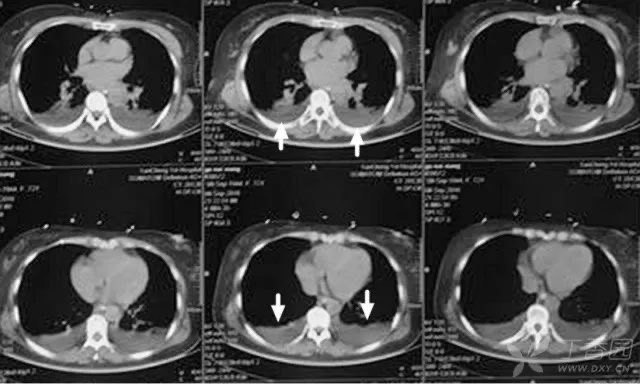

胸膜下线影:

胸膜下与胸膜平行的线状影,一般距离胸膜面下 10 mm 内;病理基础是细支气管周围的纤维化或肺泡萎陷。最初报告见于石棉肺,现认为这一现象无特异性,可见于其它肺间质纤维化疾病和病毒性肺炎愈后(SARS、H1N1 等)。

弥漫性特发性肺间质纤维化(IPF):表现为蜂窝样灶(蓝箭),并可见胸膜下线(绿箭)。IPF 平片示两肺纹理紊乱;CT 表现为双肺类网状、条索状灶,病变分布以胸膜下带较为显著。